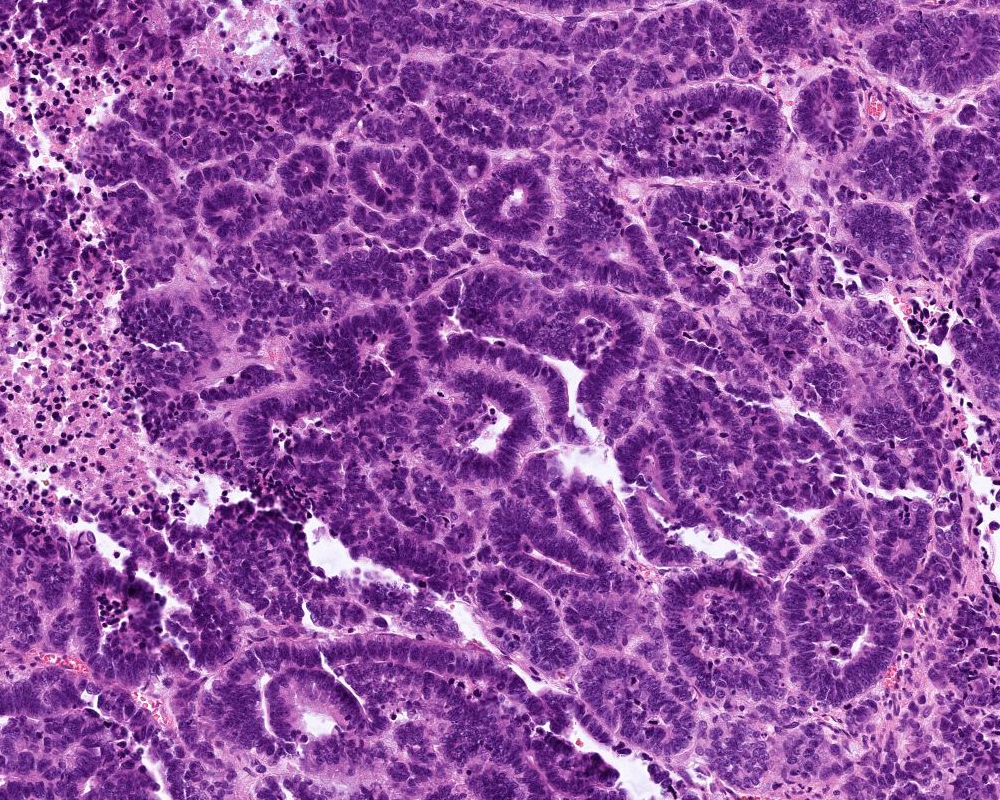

Microscopic (histologic) description

- Choroid plexus papilloma (CPP, WHO grade 1):

- Papillary (finger-like) architecture, resembling normal choroid plexus

- Single layer of cuboidal to columnar monomorphic cells

- Loss of cobblestone surface

- Mild nuclear pleomorphism, mitotic activity rare (< 2/10 high power fields), lacks necrosis

- Atypical choroid plexus papilloma (aCPP, WHO grade 2):

- Higher cellularity relative to CPP

- Moderate nuclear pleomorphism, blurring of papillary pattern

- Occasional mitoses (> 2/10 high power fields), with or without necrosis

Microscopic (histologic) images